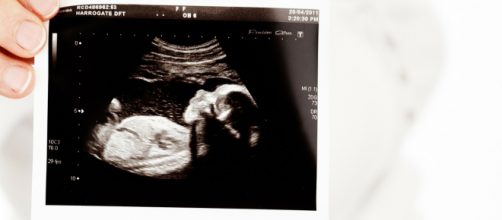

When Texas law enforcement officials tallied the victims of the massacre at Sutherland Springs, Texas they included a victim who never saw the light of day. Crystal Holcombe, the mother of five children, was killed between the pews and she was pregnant with a baby.

Since the unborn child Holcombe was carrying also died, the baby is considered a separate person. This legal classification is the law for Texas, but the actual definition of a living person and how homicide laws are applied to it differ between states.